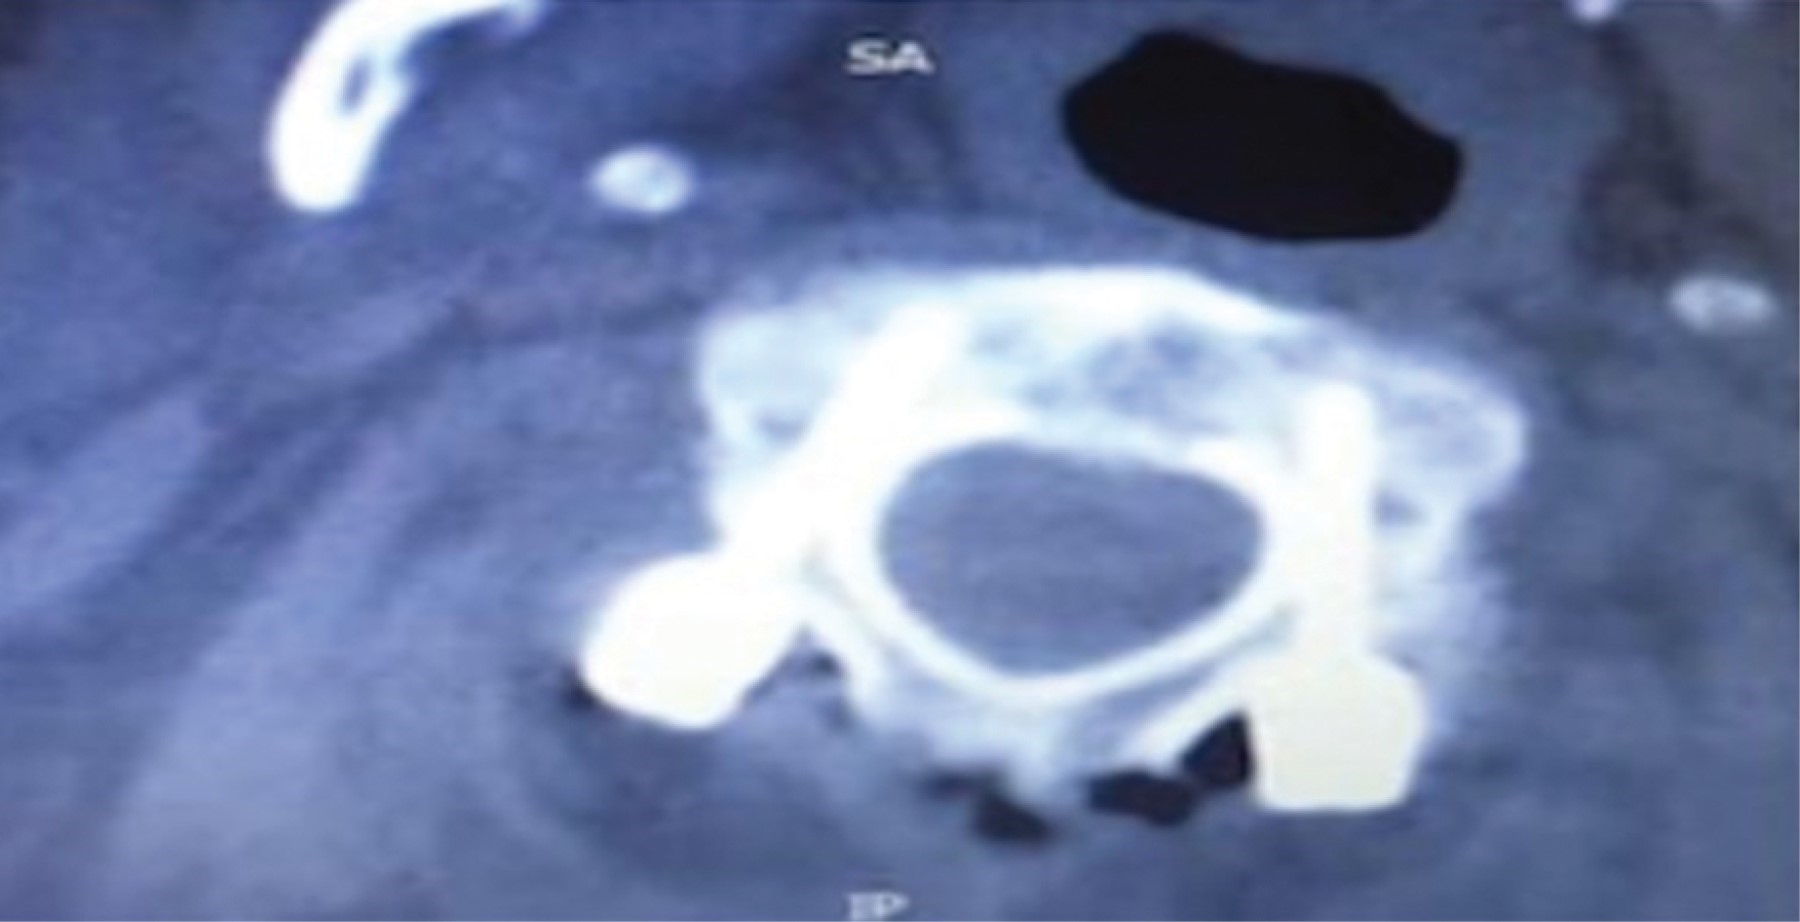

Después, localizamos el punto de entrada dividiendo en cuatro partes la imagen fluoroscópica circular, siendo el punto de entrada el cuadrante inferolateral (Figura 2). Se realiza decorticación con drill eléctrico con broca de 2 mm. Se introduce la broca manual de 3.5 mm y longitud de 18 mm, dirigiendo del cuadrante inferolateral hacia el cuadrante superomedial, siempre por debajo de la carilla articular superior hacia la base de la odontoides. Colocamos el tornillo transpedicular de diámetro de 3.5 mm y longitud promedio de 26 mm en la misma dirección descrita, observando que la punta del tornillo siempre toque o pase el borde medial de la zona de entrada.

Figura 2